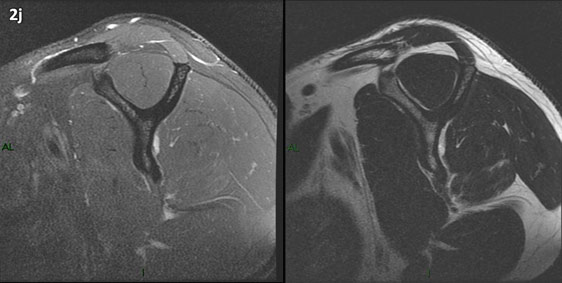

Figura 2 (a-j): Imagens consecutivas de RM no plano sagital nas ponderações T2 com supressão de gordura (DP SG) à esquerda e T2 à direita. Clique na seta para passar as imagens.

Figura 2 (a-j)': Imagens consecutivas de RM no plano sagital nas ponderaçõesT2 com supressão de gordura (DP SG) à esquerda e T2 à direita. Clique na seta para passar as imagens.

Figura 2a’ mostrando os tendões do subescapular (seta rosa), da cabeça longa do bíceps (seta verde), do supraespinhal (seta vermelha), do infraespinhal (seta laranja) e do redondo menor (seta amarela).

Figuras 2b a 2j’: Acompanhando o tendão do redondo menor (seta amarela fina) é possível notar lipossubstituição ao redor da junção miotendínea (setas amarelas grossas) e a atrofia principalmente da porção mais lateral (seta salmão). A porção mais medial (seta branca) tem volume preservado.

Repare que estas alterações também não são evidentes nas imagens com supressão de gordura no plano sagital.

Chafik et al. também relataram a presença de um pequeno nervo motor acessório em número variável que se insere na porção lateral do músculo redondo menor. O nervo acessório, ao contrário do principal, tem um curso reto e extra-fascial, sendo menos vulnerável aos efeitos compressivos. De fato, nos casos da atrofia parcial do redondo menor, é mais frequente a atrofia da porção mediodorsal com preservação da porção lateroventral, o que poderia ser explicada pela presença do ramo acessório mais lateral do nervo axilar, embora atrofia isolada do componente lateroventral tenha sido reportada em cerca de 17% dos casos de atrofia de apenas uma porção, o que pode ter sido causada por lesão do nervo acessório. No caso do paciente deste mês, a atrofia é mais evidente nesta porção mais lateral e ventral do redondo menor.

É importante que o protocolo de ressonância magnética do ombro tenha sequências ponderadas em T1, T2 ou densidade protônica (DP) sem supressão de gordura em pelo menos dois planos, idealmente nos planos coronal e sagital, para a detecção de lipossubstituição que pode passar despercebida nas imagens com supressão de gordura.

O plano sagital deve ser paralelo à superfície articular da glenoide e sempre incluir o “Y” da escápula (estendendo-se aproximadamente 4 a 5 cm medial à glenoide) para avaliação muscular adequada. Para maiores detalhes técnicos na marcação do exames de RM do ombro veja a página PROTOCOLOS / OMBRO.